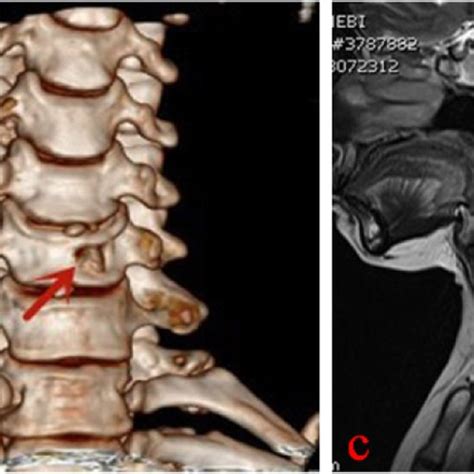

Preoperative CT images showed the formation of a disc-osteophyte ...

Ostoperative CT showed that the disc-bone complex was removed and 3D ...

Postoperative CT showing that the disc-osteophyte complex had been ...